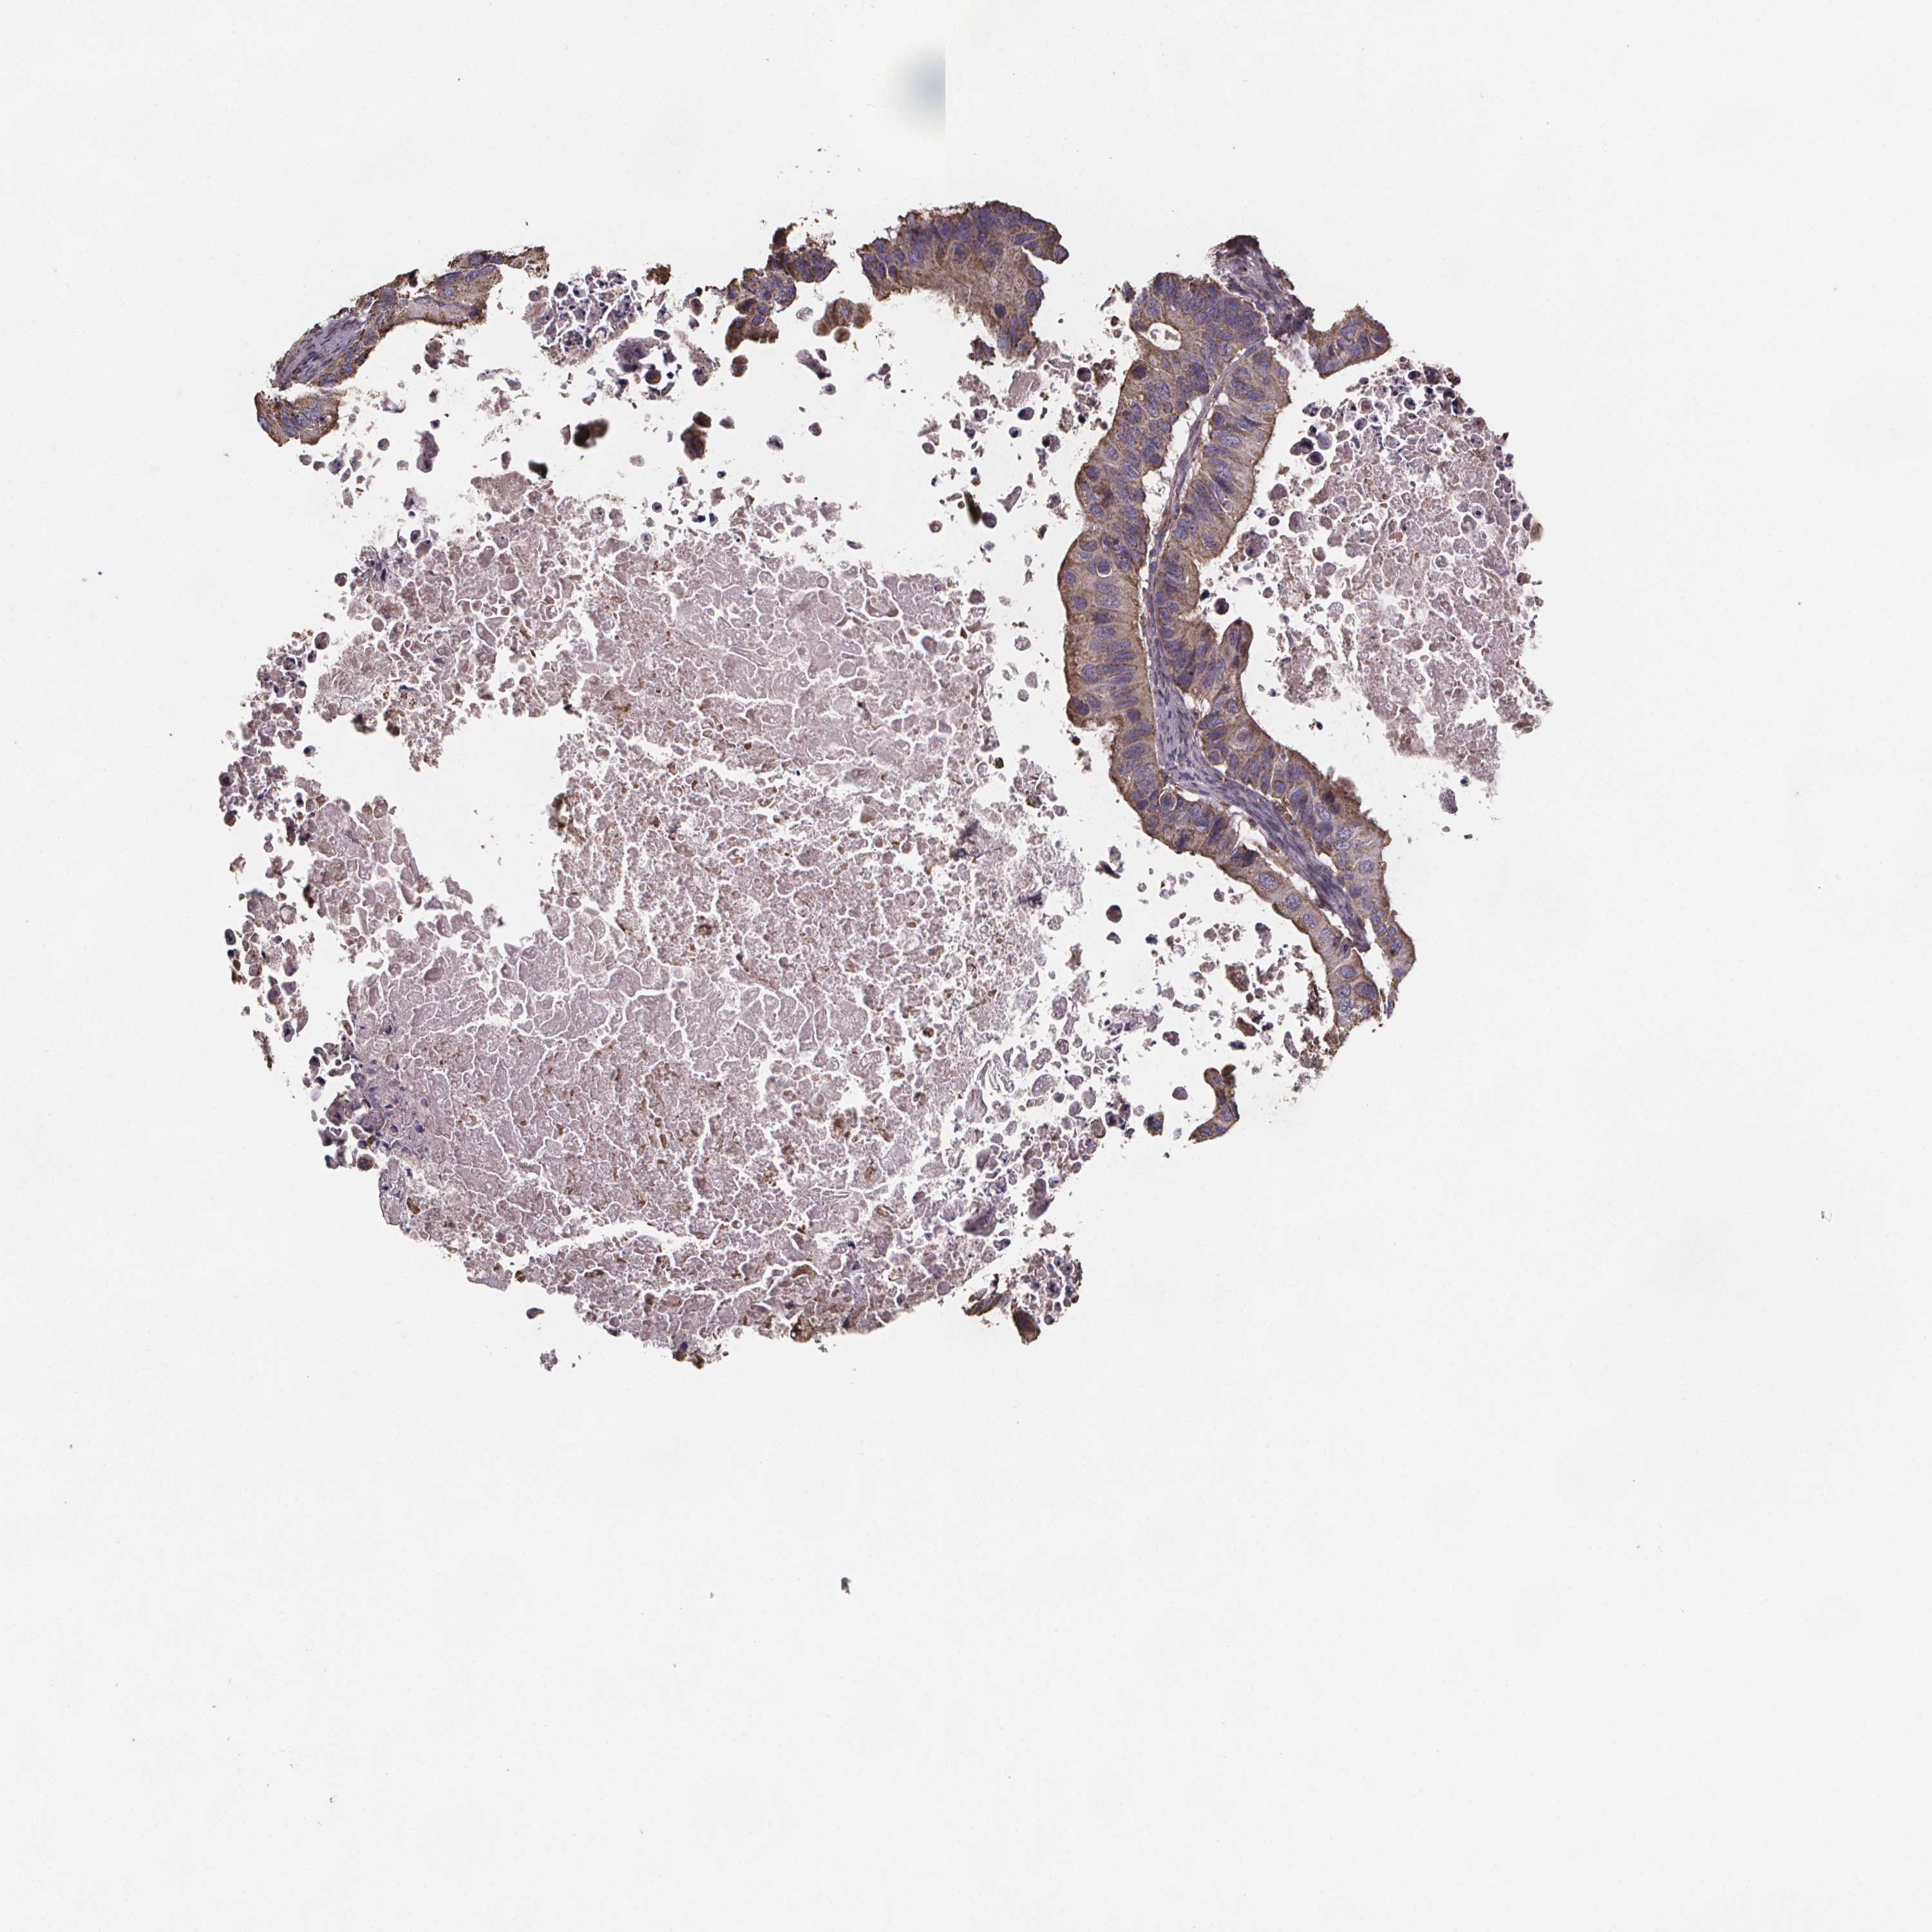

OVARIAN CANCER - Protein expressioni

A mouse-over function shows sample information and annotation data. Click on an image to view it in a full screen mode. Samples can be filtered based on level of antibody staining by selecting one or several of the following categories: high, medium, low and not detected. The assay and annotation is described here.

Note that samples used for immunohistochemistry by the Human Protein Atlas do not correspond to samples in the TCGA dataset.

Antibody stainingi

Antibody staining in the annotated cell types in the current human tissue is reported as not detected, low, medium, or high, based on conventional immunohistochemistry profiling in selected tissues. This score is based on the combination of the staining intensity and fraction of stained cells.

Each image is clickable and will lead to virtual microscopy that enables deeper exploration of all samples and also displays staining intensity scores, fraction scores and subcellular localization as well as patient and tissue information for each sample.

Antibody HPA064047

Staining

High

Medium

Low

Not detected

Intensity

Strong

Moderate

Weak

Negative

Quantity

>75%

75%-25%

<25%

None

Location

Nuclear

Cytoplasmic/membranous

Cytoplasmic/membranous,nuclear

Cystadenocarcinoma, serous, NOS

Cystadenocarcinoma, mucinous, NOS

Carcinoma, endometroid